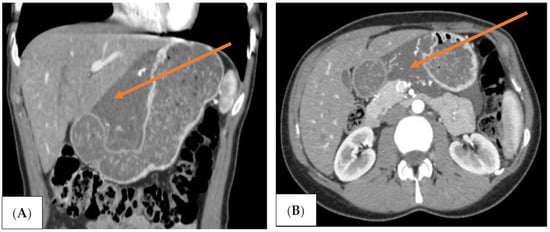

Three-phase computed tomography (CT) scan revealed an extensive mass measuring 10 × 4 cm between the left segments of the liver and the lesser curvature of the stomach. The lesion was well-defined, fluid dense, and did not contain solid elements. Within it, there were vessels with an undistorted course. The mass occupied the space in front of the body and tail of the pancreas, descending further down the back of the stomach and duodenum. (Figure 1A,B).

Figure 1. (A,B) Computed tomography (CT) image of the abdominal cavity. There is a visible mass located at the lesser curvature of the stomach (orange arrows).